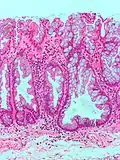

| Type de polype | Apparence histologique | Risque de malignité | Coupe histologique | Syndromes | |

| Hyperplasique | Cryptes dentées non-ramifiées | Non | ![]() |

Hyperplasique polypose syndrome | |